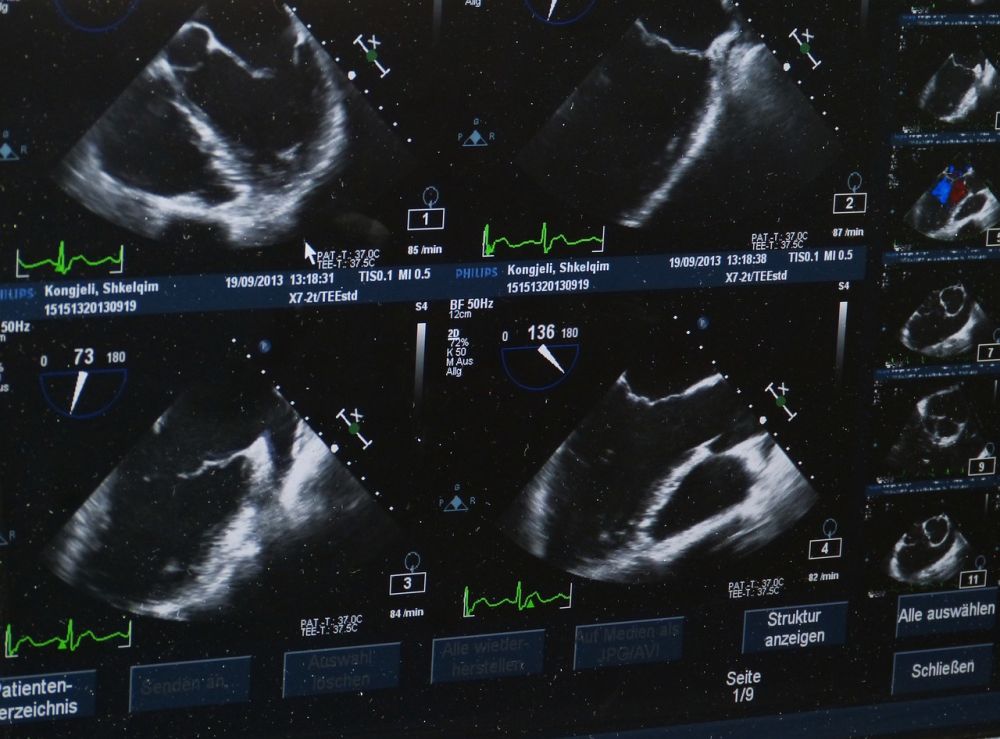

ultralydundersøgelse